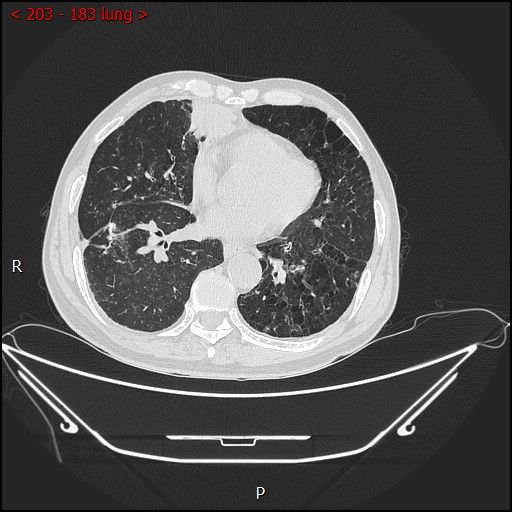

2023-07-22不开刀杀肿瘤:血管介入科开展首例CT引导下肺恶性肿瘤射频消融术

2023年7月18日血管介入科完成首例CT引导下肺恶性肿瘤射频消融术。该手术不用开刀,皮肤仅有针眼大小的穿刺针孔,术后反应轻微,恢复快,住院时间短,且与外科手术切除疗... -